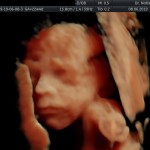

Modalidad de imagen ecográfica que permite evaluar, medir y capturar estructuras fetales superficiales e internas en 3 dimensiones (3D) y también en movimiento y en tiempo real (4D) con programas de realismo aumentado (HD LIVE) e imágenes tomografías fetales (TUI) mejorando significativamente la precisión en las mediciones fetales y la documentaciones de estructuras anatómicas.

Esta tecnología se puede utilizar desde la 6ta a la 40ma semana de embarazo.